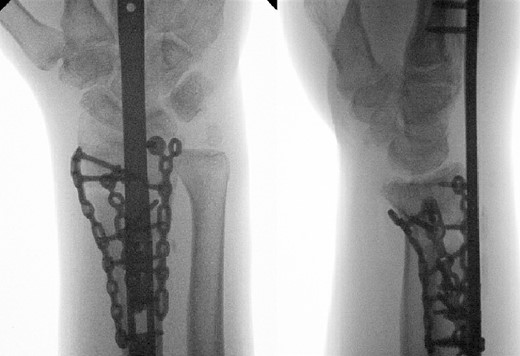

A dorsal spanning plate was planned to treat the fracture. An incision was made over the third dorsal compartment followed by release of the fourth dorsal compartment to fully visualize the fracture. Once the plate was placed, intraoperative fluoroscopy revealed that that radial styloid was still displaced. After releasing the first dorsal compartment and brachioradialis, a radiostyloid plate was then placed. Additionally, the volar ulnar corner of the radius was still not reduced properly, so a Protean fragment specific volar buttress plate was placed. Final intraoperative fluoroscopy films revealed satisfactory reduction and alignment (Figs 3 and 4).

Two weeks following the procedure, the patient returned to the clinic for a follow-up visit. The wrist was swollen and ROM was limited. Hand motor functions and neurovascular exam were fully intact. Radiographs taken in clinic showed intact hardware with healing fracture. At 2 months follow-up, radiographs showed intact hardware with interval bone bridging across fracture sites. Radiographic parameters including articular alignment, radial height, radial inclination, and volar tilt were in acceptable ranges (Fig. 5). The patient reported no concerns or complications. A computed tomography (CT) scan was obtained at 10 weeks after the procedure and confirmed adequate bony healing and alignment without failure (Fig. 6). The dorsal spanning plate was eventually removed 1 month later and 4 months since the initial operation (Fig. 7).

Radiological assessment at 2 months postprocedure with PA and lateral views.